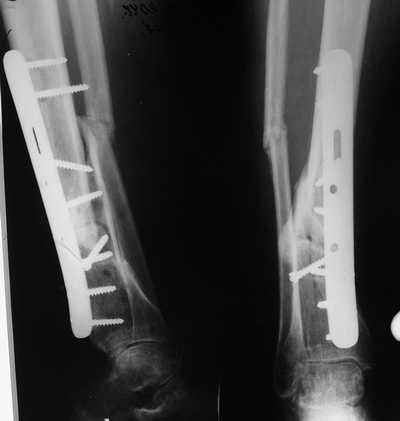

Женщина 46 лет, неудачно лечившаяся по поводу перелома голени в нижней 1\3 сначала в гипсе, поступила через 6 месяцев после остеосинтеза пластиной (рис 1). Имелась деформация в нижней 1\3 голени: варус, антекурвация, наружная ротация, два свища. Удалена пластина, дебридмент мягких тканей,

остеотомия м\б кости, аппарат Илизарова. По рентгенограммам в двух проекциях произведено планирование устранения смещений (рис 2 и 3), между вторым и третьим кольцом установлены 6 телескопических дистракторов Гесапода, данные введены в программу, и далее втечение 10 дней больная подкручивала телескопы согласно выданной компьютером инструкции. По завершению репозиции гексаподные телескопы обратно заменены на обычные штанги от аппарата Илизарова (рис 4 и 5). Еще через две недели забит гвоздь (рис 6, контроль

через 4 месяца).